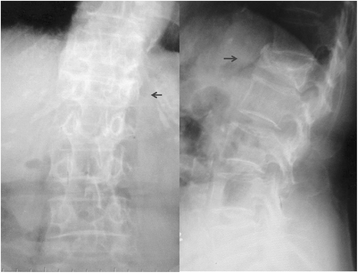

Background: Entrapment of the superior cluneal nerve (SCN) in an osteofibrous tunnel has been reported as a cause of low back pain (LBP). However, there are few reports on the prevalence of SCN disorder and there are several reports only on favorable outcomes of treatment of SCN disorder on LBP. The purposes of this prospective study were to investigate the prevalence of SCN disorder and to characterize clinical manifestations of this clinical entity.

Methods: A total of 834 patients suffering from LBP and/or leg symptoms were enrolled in this study. Diagnostic criteria for suspected SCN disorder were that the maximally tender point was on the posterior iliac crest 70 mm from the midline and that palpation of the tender point reproduced the chief complaint. When patients met both criteria, a nerve block injection was performed. At the initial evaluation, LBP and leg symptoms were assessed by visual analog scale (VAS) score. At 15 min and 1 week after the injection, VAS pain levels were recorded. If insufficient pain decrease or recurrence of pain was observed, injections were repeated weekly up to three times. Surgery was done under microscopy. Operative findings of the SCN and outcomes were recorded.

Results: Of the 834 patients, 113 (14%) met the criteria and were given nerve block injections. Of these, 54 (49%) had leg symptoms. Before injection, the mean VAS score was 68.6 ± 19.2 mm. At 1 week after injection, the mean VAS score significantly decreased to 45.2 ± 28.8 mm (p < 0.05). Ninety-six of the 113 patients (85%) experienced more than a 20 mm decrease of the VAS score following three injections and 77 patients (68%) experienced more than a 50% decrease in the VAS score. Surgery was performed in 19 patients who had intractable symptoms. Complete and almost complete relief of leg symptoms were obtained in five of these surgical patients.

Conclusions: SCN disorder is not a rare clinical entity and should be considered as a cause of chronic LBP or leg pain. Approximately 50% of SCN disorder patients had leg symptoms.